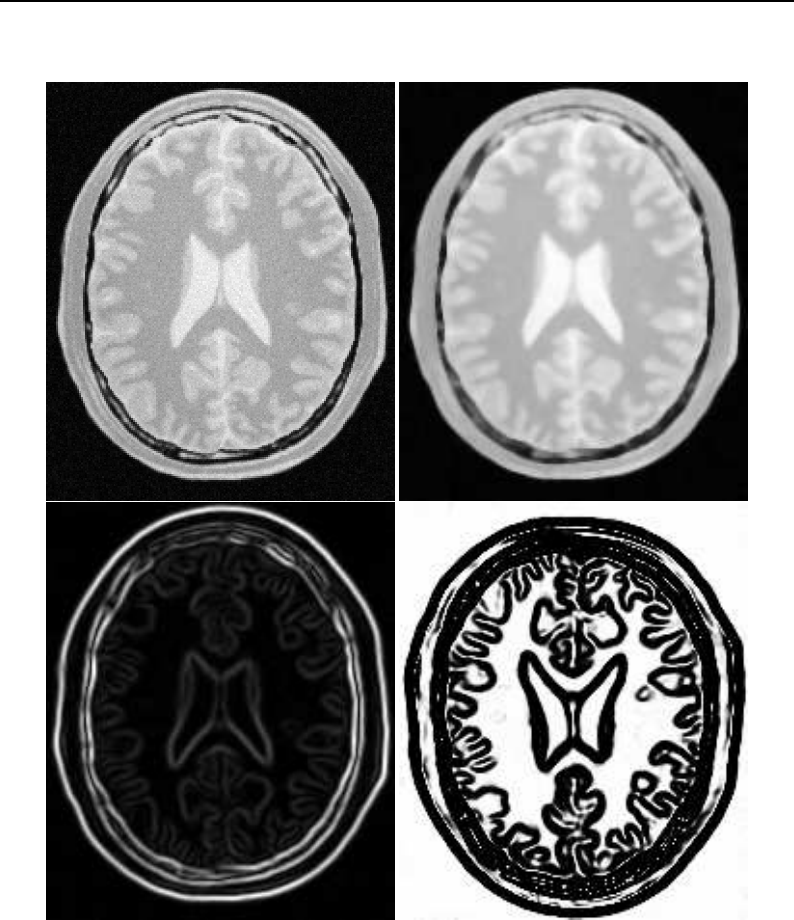

The Insight Toolkit (ITK) is an open-source, cross-platform system for medical image processing. It

provides medical imaging researchers with an extensive suite of leading-edge algorithms for

registering, segmenting, analyzing, and quantifying medical data. It is used in thousands of research

and commercial applications, from major labs to individual innovators.

The National Library of Medicine Insight Segmentation and Registration Toolkit, shortened as the

Insight Toolkit (ITK), is an open-source software toolkit for performing registration and segmenta-

tion. Segmentation is the process of identifying and classifying data found in a digitally sampled

representation. Typically the sampled representation is an image acquired from such medical instru-

mentation as CT or MRI scanners. Registration is the task of aligning or developing correspondences

between data. For example, in the medical environment, a CT scan may be aligned with a MRI scan

in order to combine the information contained in both.